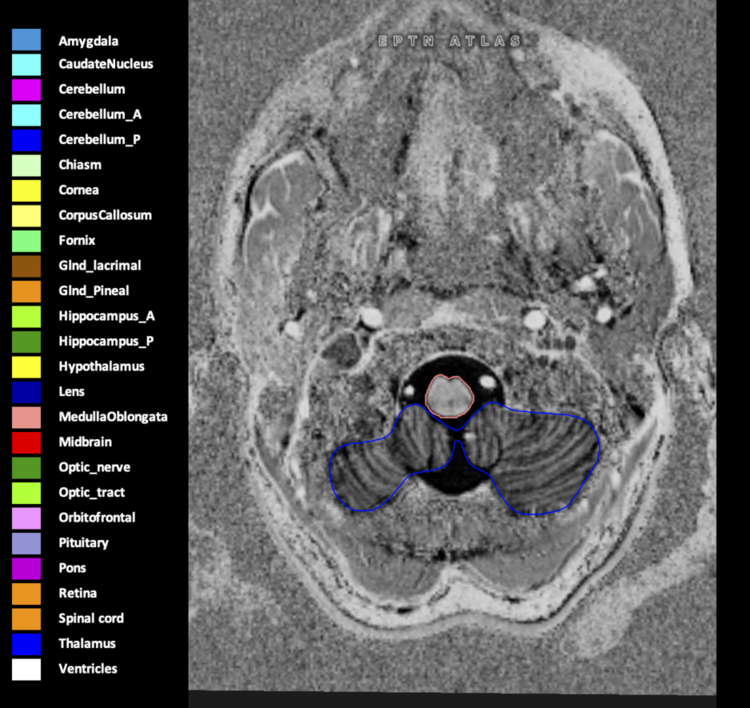

Eekers et al. have published an international neurological atlas for contouring of organs at risk in consensus with the European Particle Therapy Network (EPTN) in 2018 and an update in 2021. The purpose of this consensus atlas is to decrease inter- and intra-observer variability in delineating OARs relevant for neuro-oncology.

Included are all OARs known to be relevant for radiation-induced toxicity in neuro-oncology: brain, brainstem (midbrain, pons, medulla oblongata), chiasm, cerebellum (anterior & posterior), cochlea, cornea, hippocampus (anterior & posterior), hypothalamus, lens, lacrimal gland, optic nerve, pituitary, skin, and vestibular & semicircular canals. To further facilitate research on cognition, vision and radiological changes after irradiation of the brain, potential clinically-relevant OARs are included: amygdala, caudate nucleus, cerebellum (anterior & posterior), corpus callosum, fornix, macula, optic tract, orbitofrontal cortex, periventricular space (PVS), pineal gland, and thalamus.

We propose this atlas is used in photon and particle therapy in order to derive consistent dosimetric data. When required this atlas will be updated according to new insights.

Three-dimensional delineation of the 25 consensus OARs for neuro-oncology are shown on CT (WW/WL 120/40, 3000/600), 3T MR images, (T1Gd, T2FLAIR 1mm) and 7T MR (MP2RAGE 0.7 mm). All are presented in transversal, sagittal and coronal view.